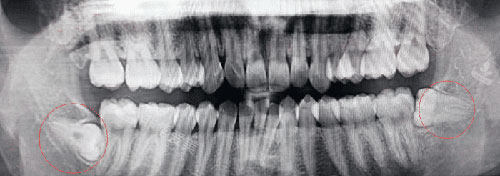

智齿牙片示意图

二、辅助检查项目:前置必备的花费构成

全景片拍摄:

作为拔智齿的基础筛查手段,可清晰呈现智齿整体位置、牙根形态及与邻牙、神经的关系,为手术方案制定提供关键依据。